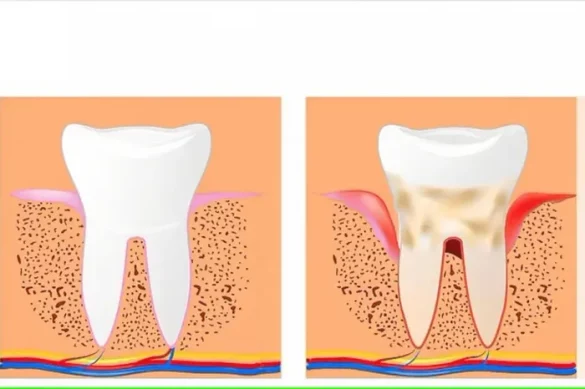

Increased Risk of Gum Disease

Gum ailment is a extreme circumstance that could damage the tissues helping your tooth. The preliminary stage, gingivitis, is marked with the aid of using red, swollen, and bleeding gums. If now no longer treated, it may increase to periodontitis, which reasons the gums to recede and might result in enamel loss. Studies display that each people who smoke and vape customers are at extra threat of growing gum ailment. In fact, studies evaluating cigarette people who smoke, vape customers, and non-people who smoke discovered that vape customers display better ranges of gum irritation than non-people who smoke, simply brief of that visible in cigarette people who smoke.

Swollen Gums: How Is It Linked to Vaping?

Swollen gums are a conventional symptom of gum disorder and inflammation. Several mechanisms provide an explanation for why vaping can motive swollen gums:

- Nicotine restricts blood flow: Less circulate method much less restoration and resistance to contamination, main to swelling.

- Chemical irritation: Vape juices incorporate chemical substances consisting of propylene glycol and synthetic flavorings. These can worsen the gums, particularly in case you vape often or use quite flavored juices.

- Reduced saliva: A dry mouth offers micro organism greater possibility to multiply. Bacteria launch pollution that inflame gum tissue, inflicting swelling.

- Disruption of wholesome oral micro organism: Vaping stresses bacterial groups withinside the mouth, developing an surroundings greater liable to disorder and inflammation. According to experts, the oral microbiome will become dangerous after publicity to e-cigarette vapor, which makes gums greater vulnerable.

Receding Gums

Chronic use of nicotine, whether or not smoked or vaped, can motive gum tissues to die and recede. Receding gums reveal the teeth roots and can bring about sensitivity and accelerated hollow space risk. In intense cases, recession can result in teeth loss.